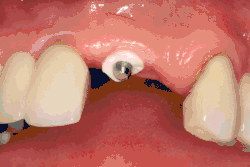

- Adaptace tkáně: Dásně se přizpůsobí kolem celého implantátu a vytvoří silný pás zdravé tkáně kolem "hojícího se pillíře. Naproti tomu může být implantát pohřben, kdy je horní část implantátu uzavřena krycím šroubem a tkáň je uzavřena tak, aby jej zcela zakryla. K pozdějšímu odkrytí implantátu je pak nutný druhý zákrok.

Po zavedení implantátu se vnitřní komponenty zakryjí buď hojivým abutmentem, nebo krycím šroubem. Hojivý abutment prochází sliznicí a okolní sliznice se kolem něj upraví. Krycí šroub je v jedné rovině s povrchem zubního implantátu a je navržen tak, aby byl zcela překryt sliznicí. Po období integrace je nutný druhý chirurgický zákrok, při kterém se sliznice odrazí a umístí se hojivý abutment.[34]:s.190-1

Protetická fáze začíná, jakmile je implantát dobře integrován (nebo je dostatečná jistota, že se integruje) a je umístěn abutment, který jej přenáší přes sliznici. I v případě časného zatížení (méně než 3 měsíce) mnoho lékařů umístí dočasné zuby, dokud není potvrzena oseointegrace (vhojení do kosti). Protetická fáze obnovy implantátu vyžaduje stejné množství technických znalostí jako chirurgická, a to z důvodu biomechanických úvah, zejména pokud má být obnoveno více zubů. Zubní lékař bude pracovat na obnovení vertikálního rozměru okluze, estetiky úsměvu a strukturální integrity zubů, aby se rovnoměrně rozložily síly implantátů.[12]:s.241–251